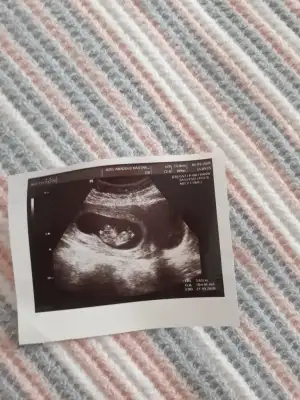

11+4 banda yorum yaparmısınız

Kaç haftalık 11 12 13 hafta olmalı nublar kapalı kafa yapısı erkek gibi tutmayabilir nub için istediğim haftalarıda paylaşınBenimde bebeğime bakarmısınız dr ters olduğu için göremedi Eki Görüntüle 2619582 Eki Görüntüle 2619582 Eki Görüntüle 2619583

6-7 hafta olmalıBen hala cinsiyet öğrenemedim canım kontrole gidemedim yani plesentaya göre tahmini yeni duydum bakarmisin 10 haftalik burdaIkra meyra